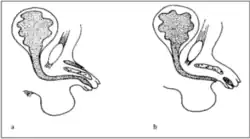

Den Abbildungen liegt folgende Typisierung zugrunde:[2]

- Typ 1 blind endende überzählige Urethra

- (a) epispade Lokalisation der akzessorischen Urethra

- (b) die akzessorische mündet an normaler Stelle (loco typico), die funktionelle Urethra hypospad

- Typ 2 komplette Duplikatur, beide Harnröhren verlaufen innerhalb des Penisschaftes

- (a) von normaler Länge

- (b) von kurzer Länge

- Typ 3 komplette Duplikation mit funktioneller Urethra und außerhalb des Penisschaftes mündender Harnröhre

- Typ 4 Duplikatur mit partieller oder kompletter kaudaler Duplikation mit zweiter Harnblase und eigener Ableitung (epispad)